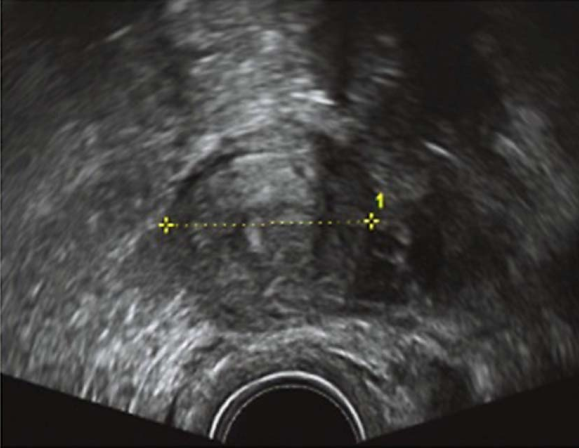

先天性无子宫经腹部超声

先天性无子宫经阴道超声